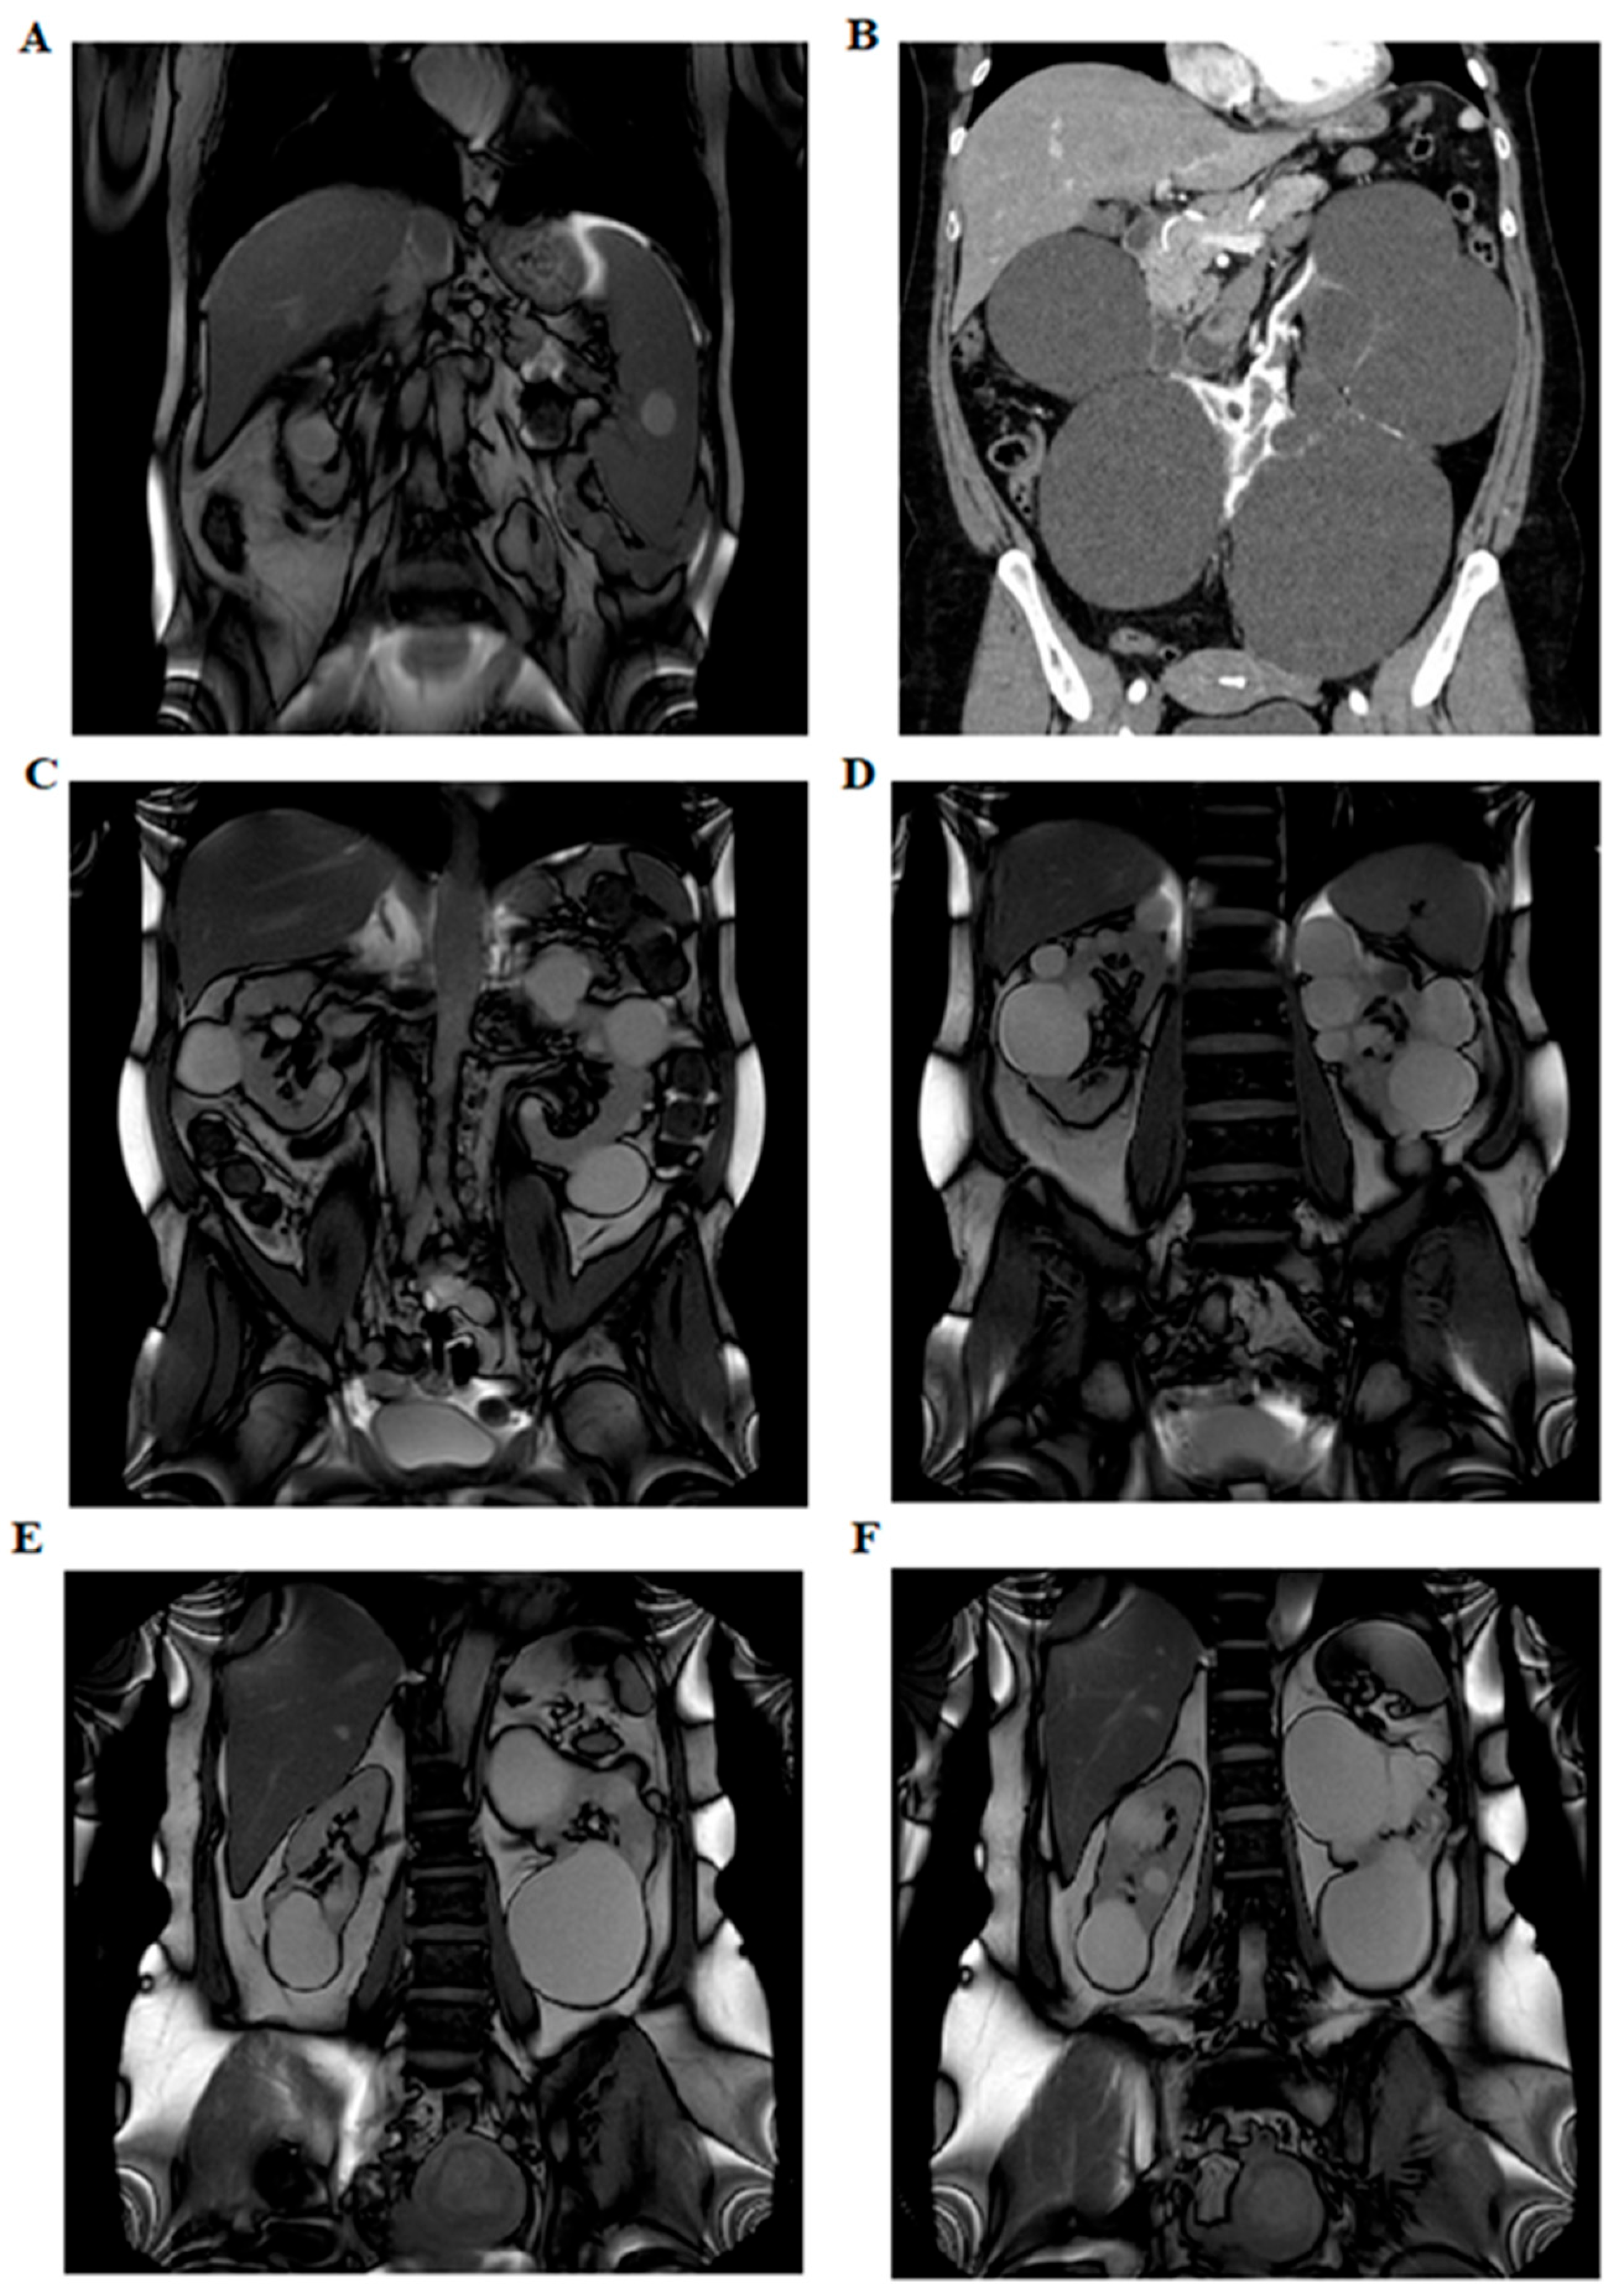

Appendix A.1.1. Pedigree BO-049

Appendix A.1.2. Pedigree BO-071

Appendix A.1.3. Pedigree BO-101

Appendix A.1.4. Pedigree BO-126

Appendix A.1.5. Pedigree BO-178

Appendix A.1.6. Pedigree BO-183

Appendix A.1.7. Pedigree BO-199

Appendix A.1.8. Pedigree BO-207

Appendix A.1.9. Pedigree BO-213

Appendix A.1.10. Pedigree BO-214

Appendix A.1.11. Pedigree BO-215

Appendix A.1.12. Pedigree BO-216

Appendix A.1.13. Pedigree BO-217

Appendix A.1.14. Pedigree BO-218